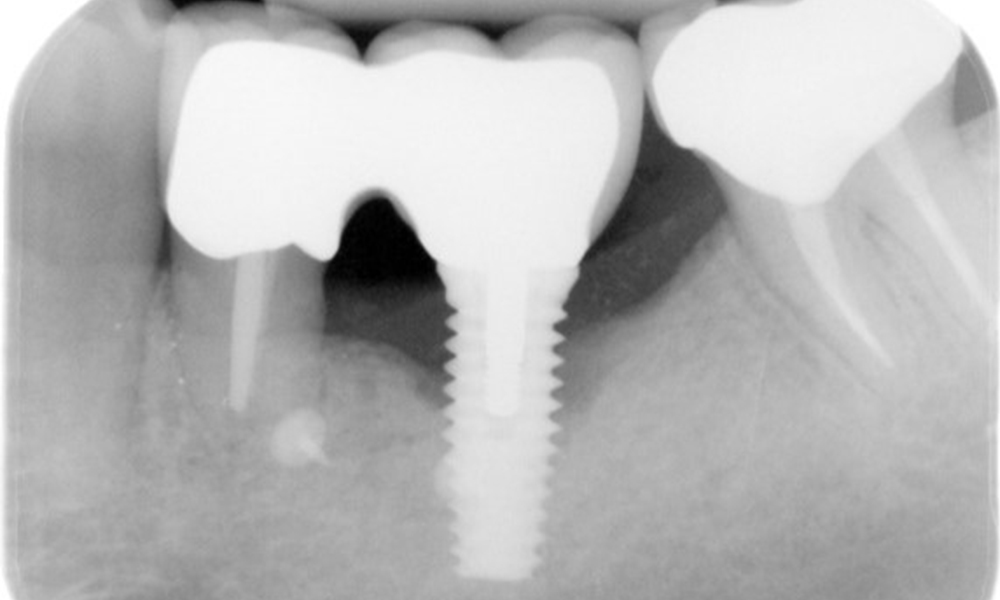

Der Patient zeigt keine besonderen anamnestischen Risikofaktoren mit spezifischen zahnmedizinischen Auswirkungen. Daher ist der aus der Mundgesundheit ermittelte Bedarf maßgebend. Hierbei zeigt sich am Implantat im 3. Quadranten ST von 5 mm und im Röntgenbild eine Zunahme des Knochenverlustes. Der Patient hat zudem eine aktuell stabile parodontale Vorerkrankung und zwei aktive initialkariöse Läsionen.

Röntgenaufnahme zeigt Verlauf des Knochenabbaus

"Die Röntgenaufnahmen zeigen den Verlauf des Knochenabbaus. OPG vom 29.06.2020 (links) und OPG vom 26.02.2024 (rechts)

Die Röntgenaufnahmen zeigen den Verlauf des Knochenabbaus im Bereich des Implantats Regio 36: ZF vom 11.02.2021 (links) und ZF vom 18.01.2024 (rechts)

OPG: 26.02.2024 ZF: 18.01.2024